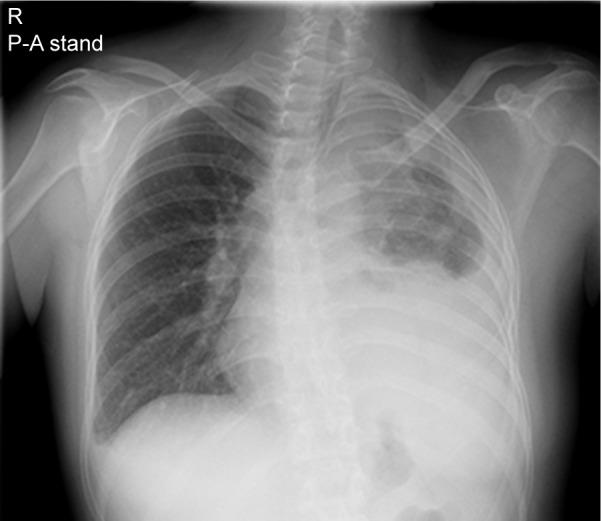

Hypoparathyroidism with sensorineural deafness and renal dysplasia (HDR) syndrome is an autosomal dominant condition caused by mutations of the gene encoding the dual zinc-finger transcription factor, GATA3. A previous study identified some patients with gene variants and breast cancer, suggesting that variants may contribute to tumorigenesis in estrogen receptor 1-positive breast tumors; however, these patients did not have HDR syndrome. A 32-year-old nonsmoking Japanese woman was histologically diagnosed with lung squamous cell carcinoma associated with HDR syndrome and a c.C952T>C (p.C318R) germline mutation in . This is the first report describing cancer in a patient with HDR syndrome. Our data indicates that mutations may be a potential therapeutic target for lung cancer.

伴有感音神经性耳聋和肾发育不全(HDR)综合征的甲状旁腺功能减退症是一种常染色体显性疾病,由编码双锌指转录因子GATA3的基因突变引起。先前的一项研究发现一些携带该基因突变的患者患有乳腺癌,这表明该基因突变可能在雌激素受体1阳性的乳腺肿瘤发生中起作用;然而,这些患者并没有HDR综合征。一名32岁不吸烟的日本女性经组织学诊断为患有与HDR综合征相关的肺鳞状细胞癌,并且其生殖细胞中存在c.C952T>C(p.C318R)突变。这是首篇描述HDR综合征患者患癌情况的报告。我们的数据表明,该基因突变可能是肺癌的一个潜在治疗靶点。